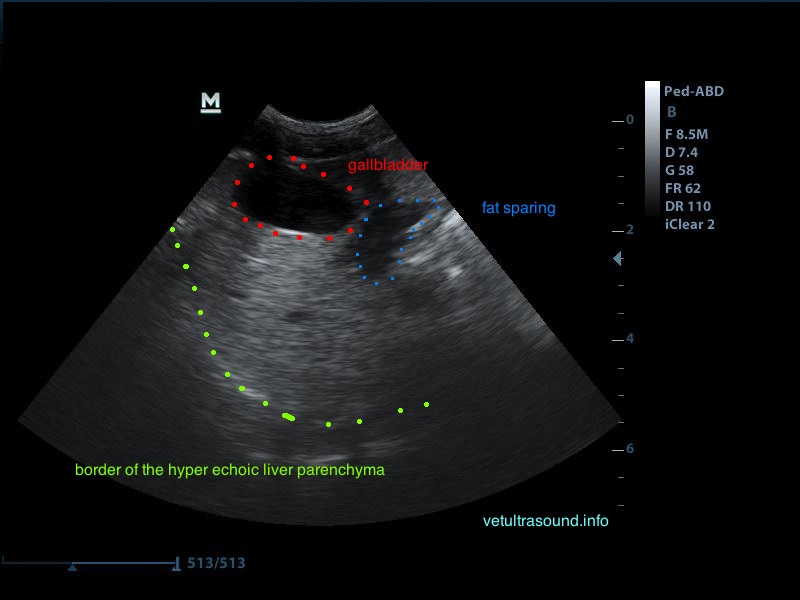

Το fat sparing είναι μία έκφραση που χρησιμοποιείται κατά την υπερηχοτομογραφική εξέταση, σε περιπτώσεις λιποείδωσης του ήπατος για να περιγράψει περιοχές του ηπατικού παρεγχύματος στο οποίο δεν έχει γίνει εναπόθεση λίπους. Πολλές φορές μπορεί η λιποείδωση να είναι σε τέτοιο βαθμό ώστε όλο το ήπαρ να είναι ομοιόμορφα υπερηχογενές και να εντοπίζονται εστιακές ή πολυεστιακές περιοχές υποηχογένειας και η διαφοροποίηση του ποιά από τις δύο απεικονίσεις είναι φυσιολογική να είναι δύσκολη. Αυτή η εικόνα μπορεί να επηρεάσει και την εκλογή του σημείου που θα πρέπει να γίνει βιοψία ή FNA.

Το ήπαρ εμφανίζεται υπερηχογενές και ο ήχος εξαντλείται καθώς περνάει μέσα από αυτό. Δεν είναι εύκολη η διαφοροποίηση του τοιχώματος της πυλαίας φλέβας σε σχέση με το υπόλοιπο παρέγχυμα.

Αντίθετα στο τμήμα που δεν έχει γίνει εναπόθεση λίπους είναι εύκολη η απεικόνιση του τοιχώματος της πυλαίας φλέβας.

Δεν προκαλεί συμπίεση των γύρω ιστών ή αγγείων (mass effect) το υγιές τμήμα του ηπατικού παρεγχύματος.